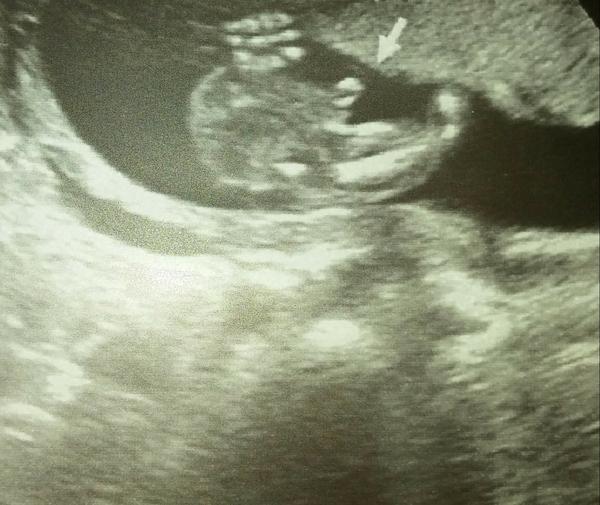

Ahoj maminky a budoucí maminky 😉 Prosím, poradila byste mi některá, co vidíte na fotce z ultrazvuku ve 20. týdnu za pohlaví? Určitě jste foteček viděly už mraky, proto vás žádám o radu...Nechci nikoho ovlivnit, proto svůj tip řeknu později 🙂 Děkuju moc!!!

@barbucha123 kluk🙂

@barbucha123 jasnej klucina

@barbucha123 urcite kluk